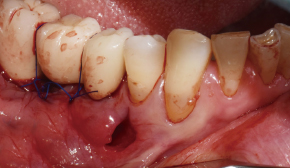

6. 골이식 후 터널 공간이 메워짐

7. 1차 봉합